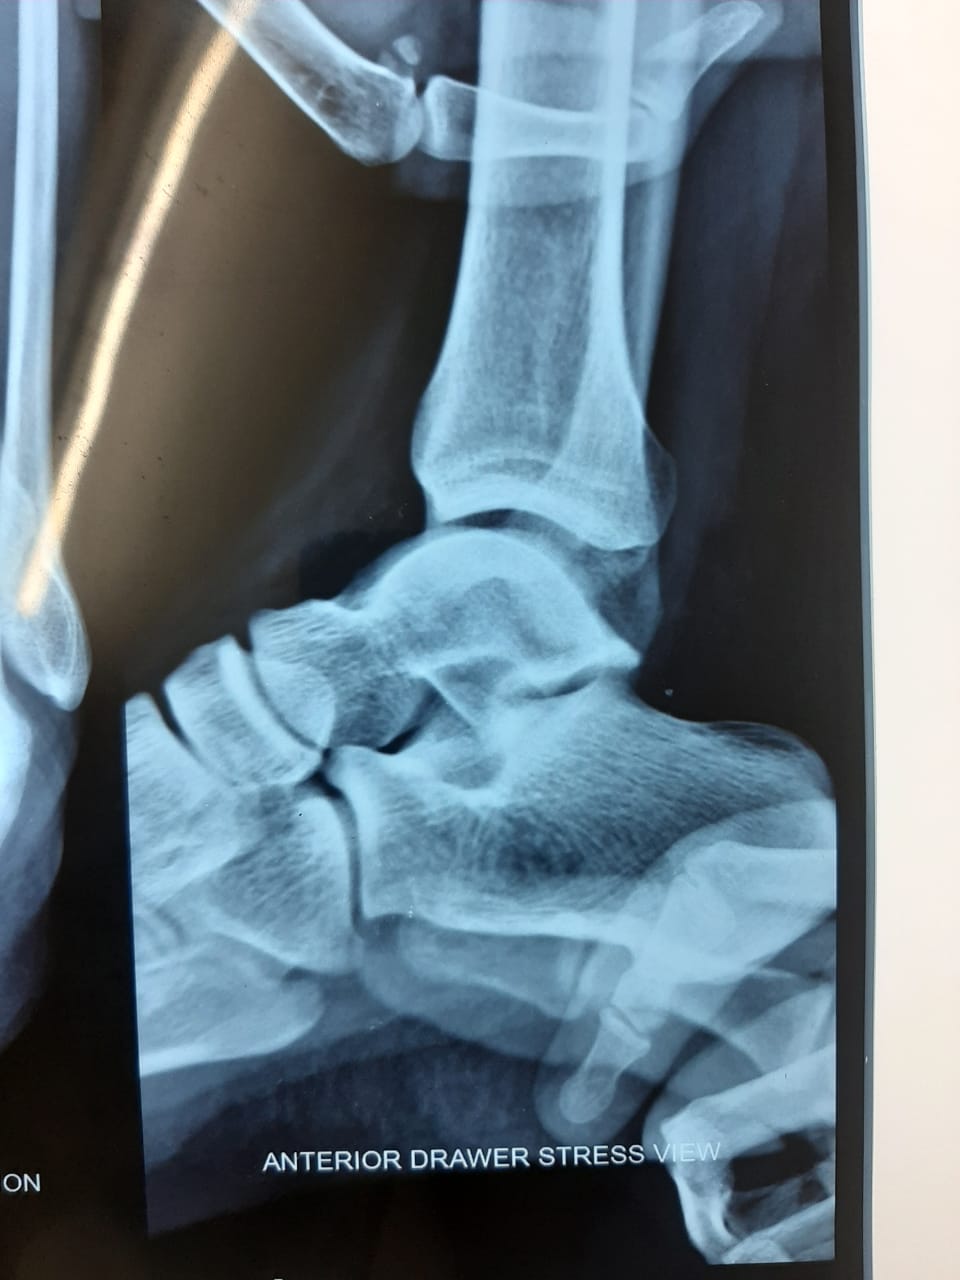

Complex Atypical Rotational Ankle Fracture Surgery

Dr Girish Motwani, one of the best foot surgeon in Nagpur, treated successfully a 30 year old guy with a history of a road traffic accident. He had...